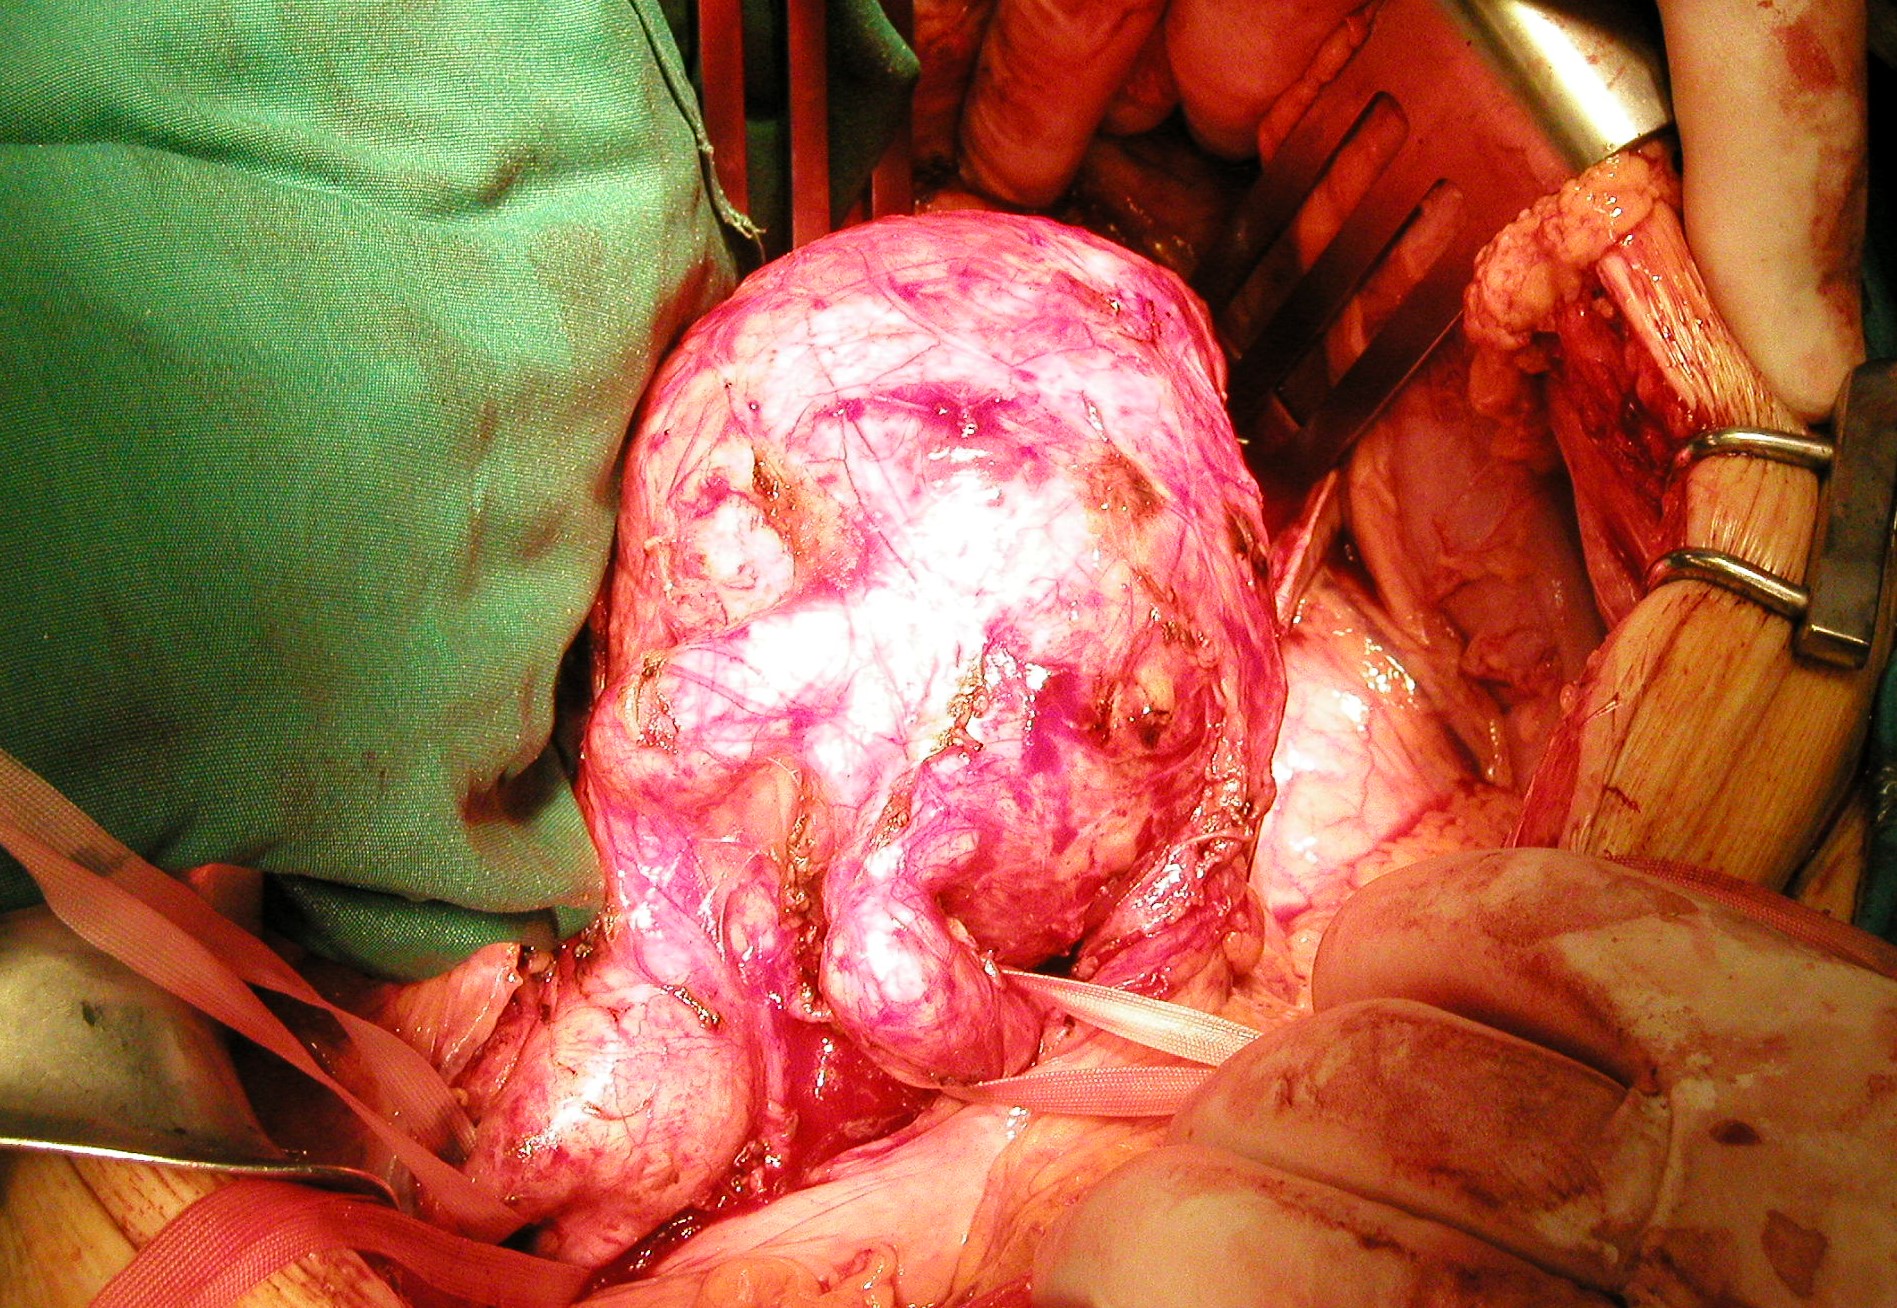

Επιπρόσθετο ανώνυμο φωτογραφικό υλικό

από την αντιμετώπιση ανευρυσμάτων της κοιλιακής αορτής και των λαγονίων αρτηριών

από το προσωπικό μου αρχείο στα Πανεπιστημιακά Νοσοκομεία Λάρισας και Ιωαννίνων

• Περιπτώσεις ανευρυσμάτων κοιλιακής αορτής